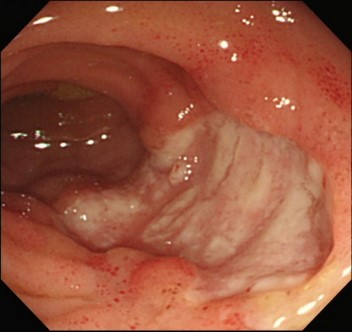

また、逆流性食道炎といった内臓病変を合併することが多いです。

逆流性食道炎

これらを主症状といい、他にも、腸管病変や

腸管病変:https://www.hosp.hyo-med.ac.jp/disease_guide/detail/150